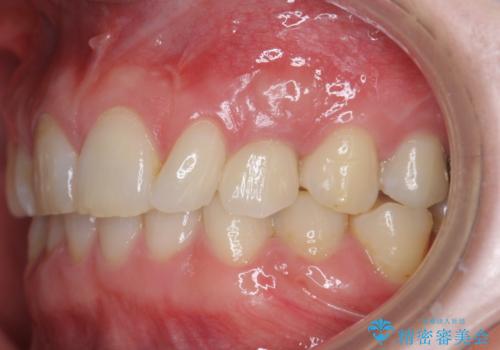

前歯のインプラント治療は骨量・歯肉の厚み・インプラントの方向をしっかりと計画することで、審美的で長持ちを期待できるような仕上がりとなります。

- 6ヶ月

- 55万円費用は治療当時の料金となります